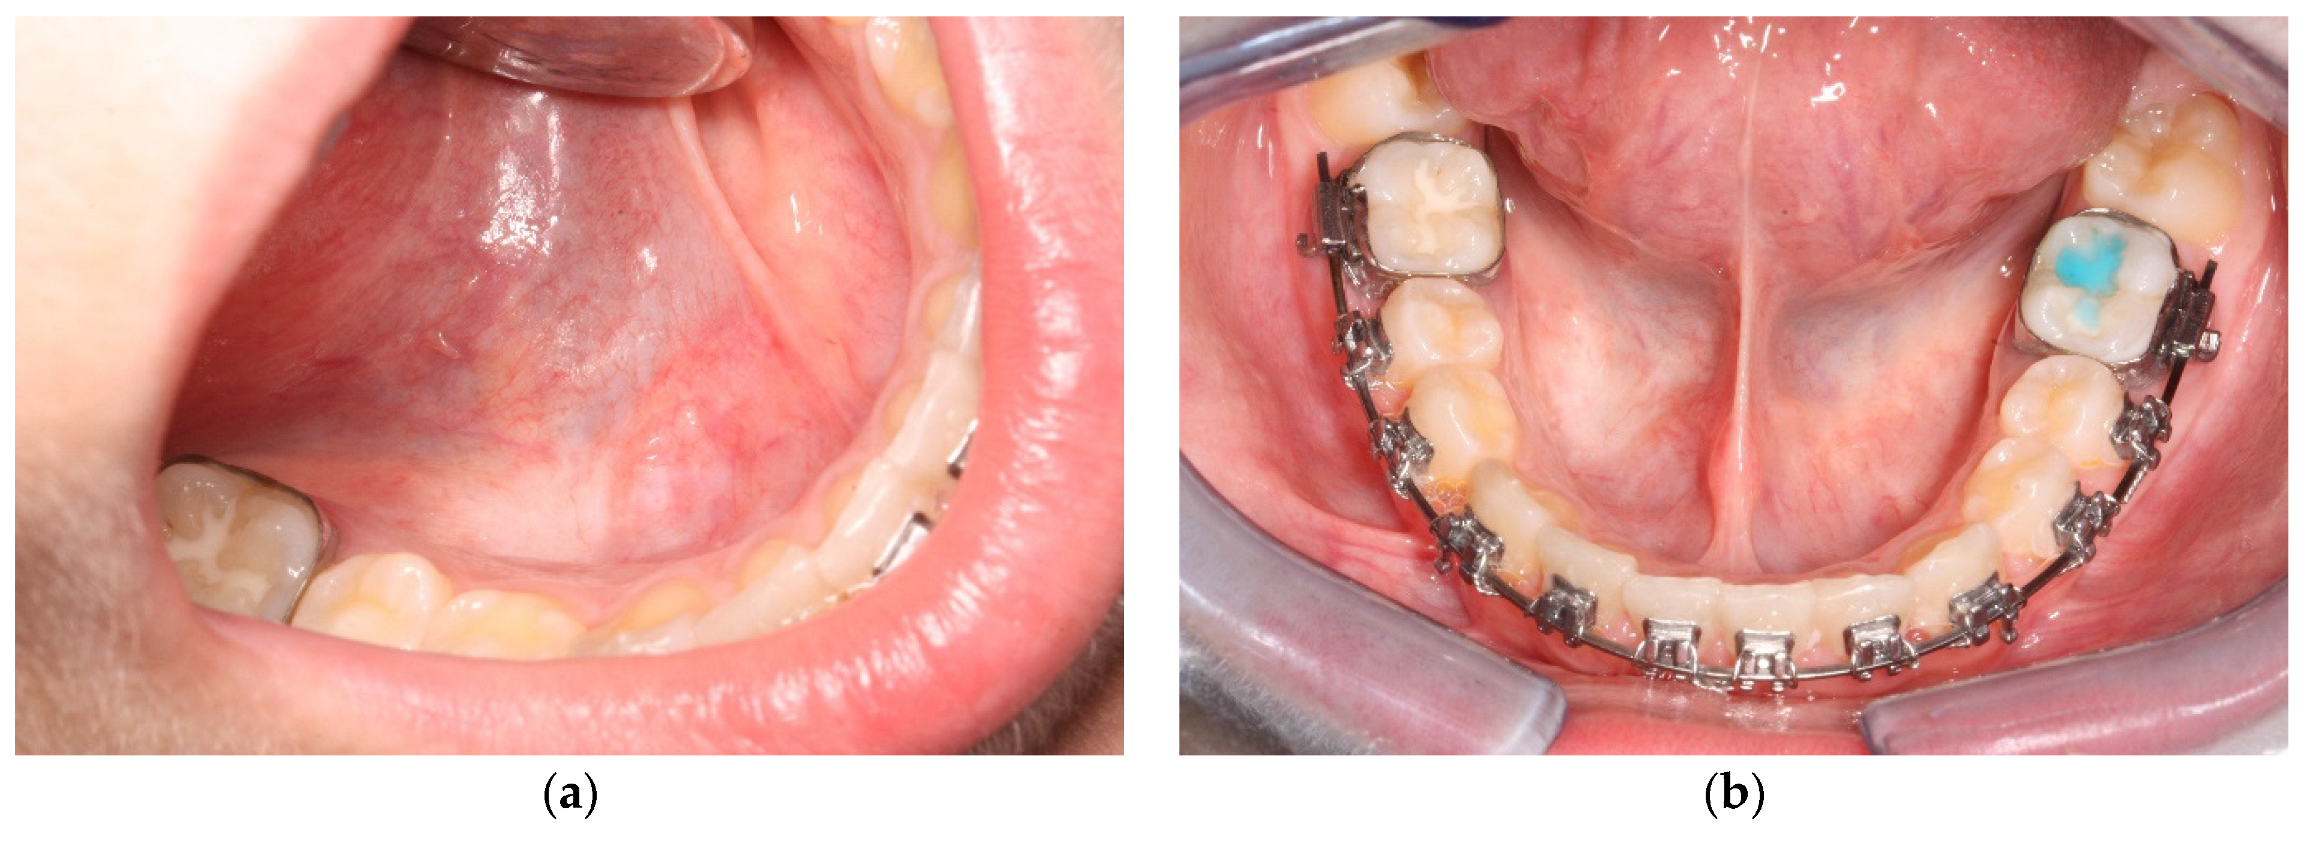

3. Results